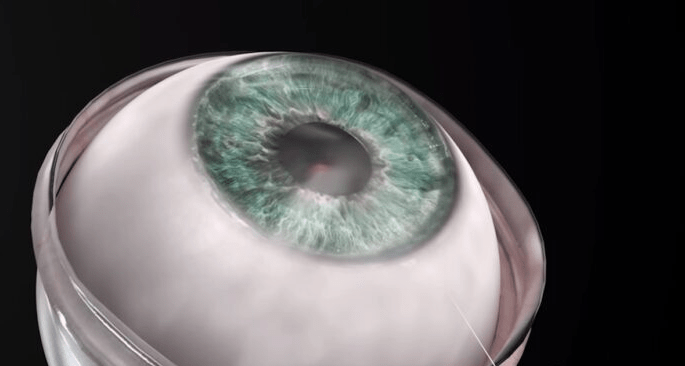

75-ročný muž je vôbec prvým pacientom, ktorý dostal implantát nedávno vyvinutej umelej rohovky a pacient opäť dokáže vidieť svoju rodinu. Chlapík dokonca úspešne absolvoval klasický test, ktorý vykonáva lekár s pacientom tak, že pacientovi ukáže tabuľu s číslicami a písmenami a skúša ho či je schopný prečítať ich.

Rohovku vyvinula izraelská firma CorNeat a táto ich rohovka sa dokáže spojiť s ľudským tkanivom. Znamená to, že rohovka dokáže úplne nahradiť poškodenú alebo chorobou zničenú túto dôležitú časť oka. „Chirurgický zákrok bol priamy a predčil všetky naše očakávania,“ povedal profesor Irit Bahar, riaditeľ oftalmologického oddelenia.

„Okamih, keď sme zložili obväzy z očí pacienta, bol to mimoriadne emotívny okamih. Sme hrdí na to, že sme v čele tohto vzrušujúceho projektu, ktorý je skutočne zmysluplný a ktorý ovplyvní životy miliónov ľudí,“ povedal šťastný Irit. Rohovka je takzvaný číry štít, ktorý chráni prednú časť oka a môže sa z rôznych dôvodov poškodiť alebo zdegenerovať. Doteraz sa ešte nikdy nepodarilo vykonať takto úspešnú operáciu.

„Po rokoch tvrdej práce, keď som videl ako kolega s ľahkosťou implantuje CorNeat KPro a bol som svedkom toho, ako pacient nasledujúci deň opäť videl, bol to skutočne elektrizujúci moment a veľmi dojímavý. V miestnosti sa každý pri pohľade na muža rozplakal,“ dodal na záver spomínaný profesor.